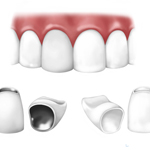

CORONE

Le corone sono protesi per denti singoli dei quali e' conservata la radice. Le corone servono a rimodellare la forma del dente e migliorano la funzionalita' e l'estetica.

La funzione della corona e' quindi quella di proteggere e ripristinare la funzione, la forma ed il colore del dente compromesso e solitamente si ancorano al dente opportunamente preparato (moncone).

I materiali con cui vengono realizzate sono diversi:

- lega bio medicale

- zirconia

- ceramica integrale

- lega nobile oro e porcellana

Ogni soluzione viene studiata dai nostri medici sulla base delle esigenze del singolo paziente.